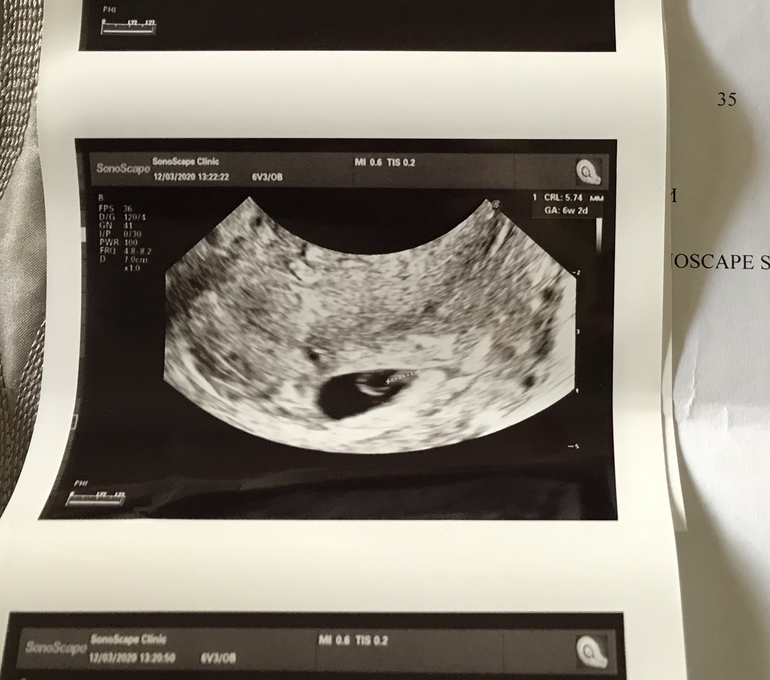

Сегодня пошла в другую клинику к мужчине. Всю ночь не спала, приехав, расплакались прям на кушетке, так мне тяжело было. Он сказал, что так случается и след беременность будет хорошей, достал датчик и начал смотреть. А потом поворачивается ко мне и говорит -я вижу эмбрион КТР 5,7 мм. ПЯ 21 мм (вчера 19 было) и желточный мешок 5 мм ( вчера 4 мм) ритмичное сердцебиение, поворачивает ко мне экран и я тоже отчётливо вижу как пульсирует сердечко моей бусинки. Тут меня уже накрыли слёзы радости. Мне хотелось обнять этого узиста)) Когда успокоилась спросила как такое возможно? Он говорит -узисты разные, бывают криворукие.

По УЗИ беременность 6, 2 недели.